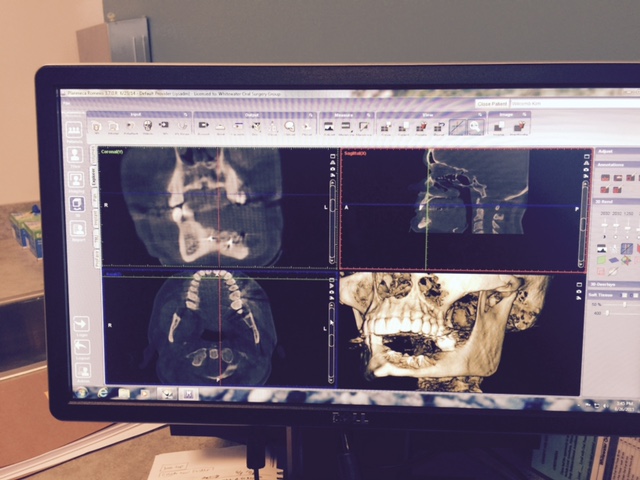

As most of you know, over the last year or so Kim has been battling medical issues after finding a Giant Cell Granuloma tumor in her bottom left jaw. Giant Cell Granuloma tumors are bone eating and although the original tumor was benign, the only way to ensure that it would stop growing or continuing to eat the bones in her jaw was to remove it. Of course, with tumor removal in the jaw came the loss of teeth and bones. After the first surgery in December of 2014, Kim faced the challenges of recovery plus an additional bone graph surgery in July of 2015 where part of her hip bone was surgically removed and placed in her jaw. After facing yet another round of recovery, this time in both her hip and her jaw, in December of 2015 the doctor's found a new tumor on the right side of her jaw that seems to be of the same type as the previous.

With finding the second tumor, Kim faces an uncountable amount of hurdles in the near future, the first being a biopsy. Most people might consider this an easy task, but because of the placement (between tooth 28 & 29 near the rear of the mouth) this biopsy requires tongue entry and will provide Kim with immediate loss of the nerve on the bottom right side of her mouth, the same way it did with the left. Tongue entry will also lead to immediate speech impairment, far worse than she has faced this far. Speech therapy will too come with a cost.

Following the biopsy, and if the doctor's anticipations of it being a second Giant Cell Granuloma tumor are true, that tumor, along with the teeth and part of the jaw it effects will need to be removed. At that point, Kim will have (hopefully) two remaining teeth in her bottom jaw.

In anticipation of the second tumor, Kim is still needing to address the reconstruction of the removal of the original tumor. At this stage, one-year post surgery, the plan is to begin the preparation for porcelain implants, or a new set of teeth. In order to do this, Kim will face a third surgery in which five metal posts will be implanted into the graphed bone in her jaw. This surgery cost is roughly $9,795. However, the quote only includes 30 minutes of general anesthesia, and the doctors anticipate surgery could take up to an hour and a half.